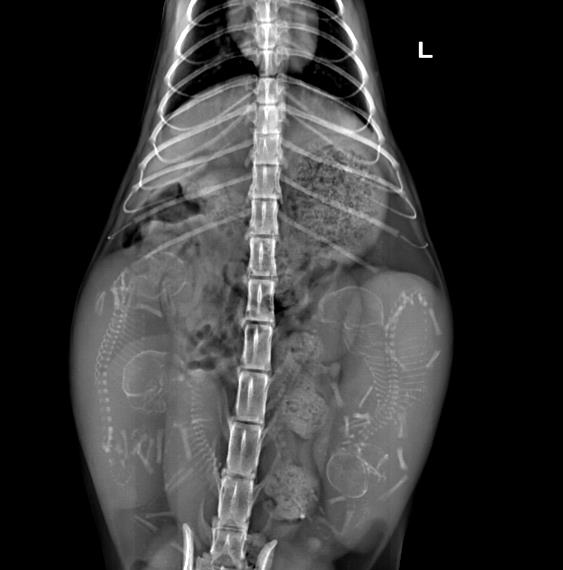

X线拍片检查:可判断胎儿体格大小、胎儿数量及胎位。在有些情况下,如果子宫内有气体或者胎儿颅骨塌陷或者其他骨头的位置出现异常,则说明发生了胎儿死亡。也可判断产道的大小与形状。